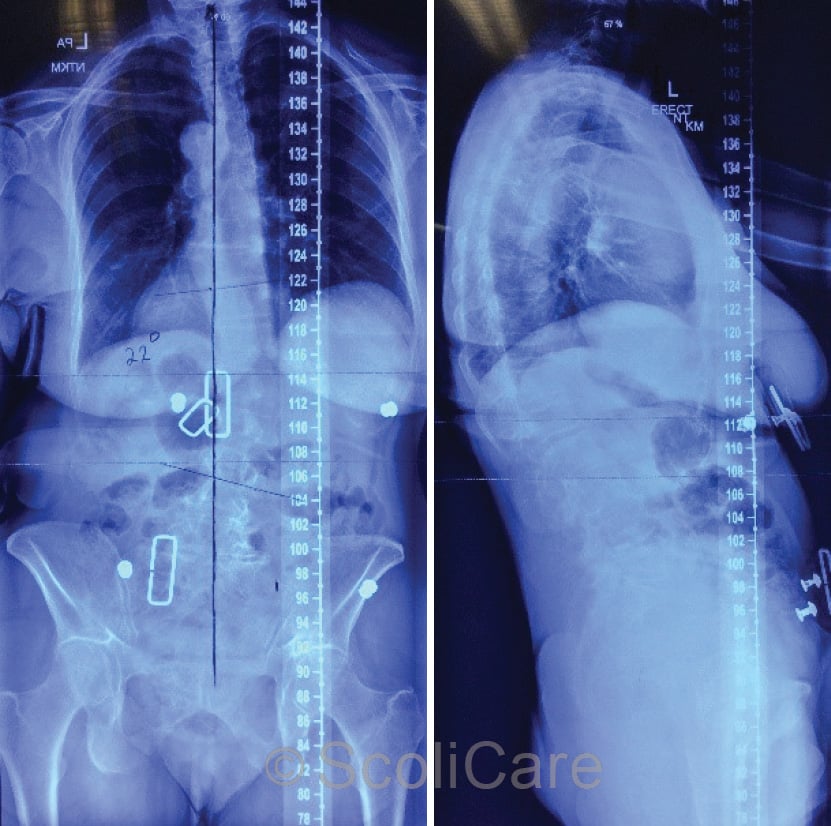

Scolibrace.com